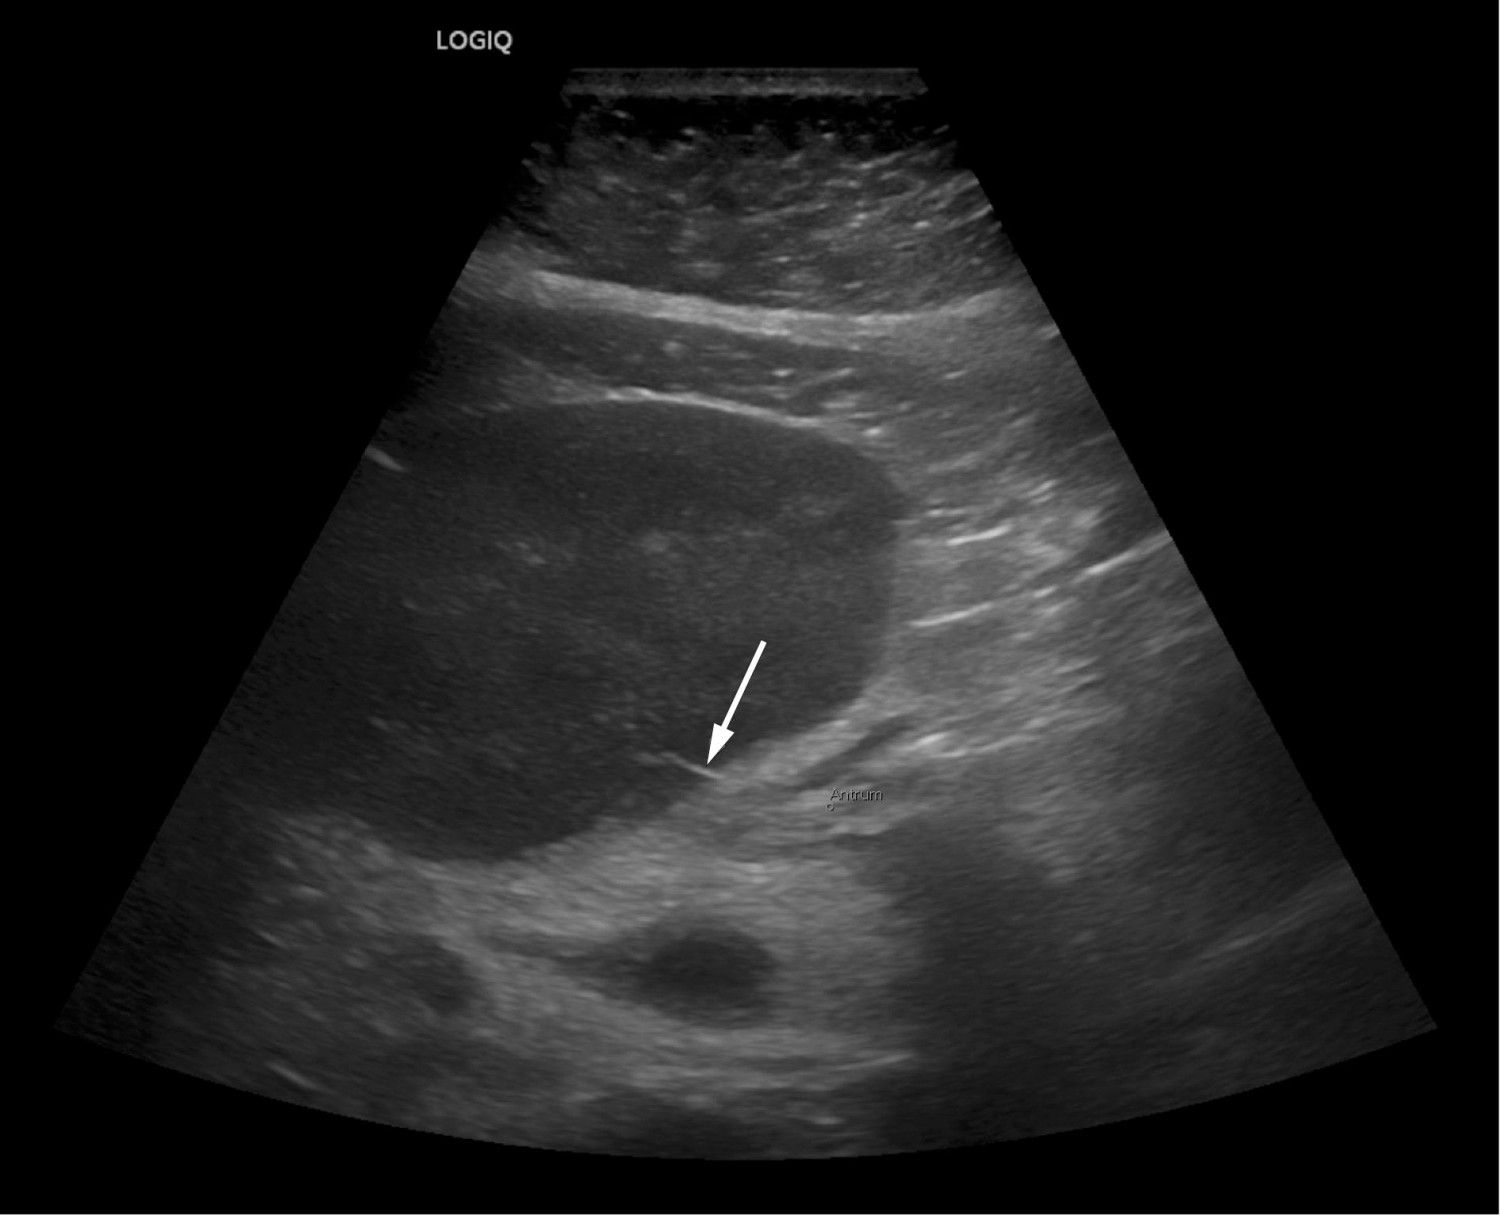

En ny granskning av CT-undersøkelsen påfølgende dag vakte mistanke om et fremmedlegeme i relasjon til leverabscessen. Fremmedlegemets tetthet og utseende kunne passe med et fiskeben. Klinisk mistenkte man perforasjon fra ventrikkelen. Ultralyd, som ble utført i forbindelse med anleggelse av dren til abscessen, bekreftet mistanken om et fremmedlegeme (figur 2). Det kom spontant blodtilblandet pusslignende væske på drenet, og man sikret prøver for bakteriologisk bestemmelse. Gastroskopi dagen etter viste normale forhold, og man så ingen mulighet for å fjerne fremmedlegemet.